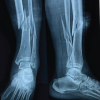

As the treating team considered the stem to be stable, with a fracture evaluated as being located distally to the area of fixation (Unified Classification System [UCS] Type C) [17], plate fixation was chosen. Open reduction and internal fixation of the fracture was performed through a subvastus approach, with reduction and fixation by a cable cerclage (Cable System 1.7 mm, DePuy Synthes, Zuchwil, Switzerland) and application of a lateral neutralization plate (non-contact bridging [NCB] Periprosthetic Femur Plate System 18 hole, Zimmer Biomet, Zug, Switzerland), fixated distally with screws and along the level of the stem with further cable cerclages (Cable System 1.7 mm). Postoperatively, the patient was mobilized in a wheelchair, as full weight-bearing was not recommended and as it was not possible to implement partial weight-bearing. Wound healing was uneventful. The radiological follow-up after 8 weeks showed intact material without evidence of loosening (Fig. 1c). Mobilization under full weight-bearing with support by physical therapy was then attempted. Four months postoperatively, the radiological follow-up showed a general atrophy of the cortical bone, which was accentuated at the lateral cortex, underneath the plate (Fig. 1d). Mobilization was hampered due to thigh pain, which had been interpreted to be caused by muscle atrophy. Thus, further physical therapy was recommended. As the impaired mobility caused difficulties attending consultation at the hospital, no further follow-up visits were planned. Due to increasing thigh pain, the patient was readdressed for evaluation by her general practitioner 4 years after the operative treatment of the PPF. Not having been mobilized outside a wheelchair in the meantime, the patient showed bilateral hip and knee flexion contractures. Consequently, she was unable to stand, disregarding the issue of thigh pain. Radiologically, there was now pronounced atrophy of the cortical bone of the femur, particularly of the lateral cortex under the plate (Fig. 1e). An infection was considered unlikely, as there was no pain at rest, as the soft tissues were inconspicuous, as the fracture had healed, and as there were no general symptoms. A single-photon emission computed tomography (CT) showed avascular areas of cortical bone underneath the plate (Fig. 3). The CT better illustrated a general atrophy of the femur with thinning of the bone cortex in comparison to the contralateral femur (Fig. 4 and 5). There was, however, no sign of loosening of the stem. Considering comorbidities, very limited potential for recovery, and the patients’ desire for no more surgery, the option of a revision was rejected, accepting the present situation. The patient died 7 months later.

Figure 4: Axial computed tomography (CT)-scan images illustrating the cross-section of the femoral diaphysis of the patient described, at the level of the yellow line in Fig. 1. In (a) at the time of the periprosthetic fracture. In (b) 4 years after internal fixation with a lateral plate. Note general atrophy with thinning out of the cortex. In the area under the plate (ar-row), there were areas of necrosis, with no detectable bone metabolism in a single-photon emission CT. The quality of the image in (b) is reduced due to artifacts caused by the im-plants and due to the movement of the patient during the procedure. Only the geometry of the bone may be compared. The apparent density of the bone is affected by differing acqui-sition protocols as well as due to artifacts induced by the implants, limiting comparison of the density

Figure 5: Computed tomography scan images 4 years after fixation of the periprosthetic fracture of the left femur after cemented hemiarthroplasty of the hip in the patient described, illustrating the cross-section at the level of the yellow line in Fig. 1, for both the right (a) and the left (b) femur. Note the general atrophy of the bone of the left femur, compared to the thickness of the cortex of the right femur, which may be considered normal at such age in females, despite immobilization. There nevertheless is a cancellous transformation at the inner cortex of the right femur, typical for endosteal resorption, as expected after prolonged unloading, the patient having never regained walking ability.